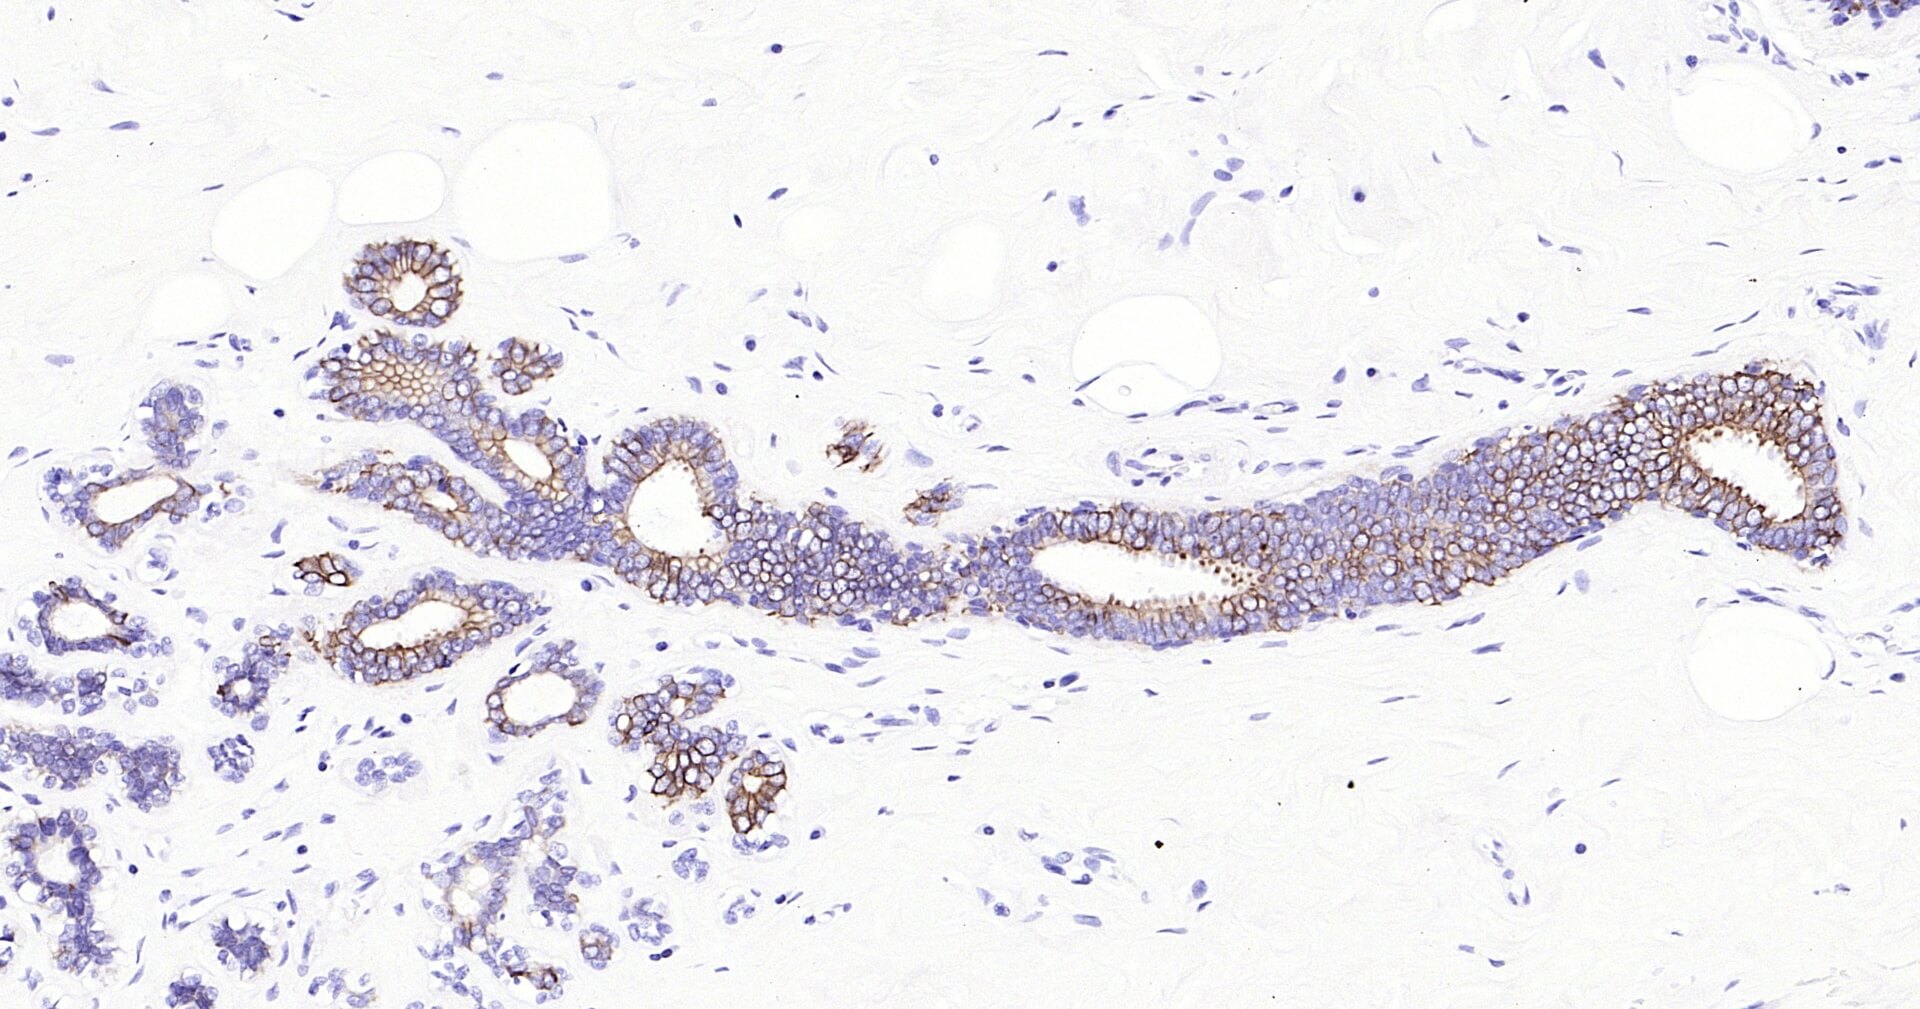

Immunohistochemical analysis of paraffin embedded human breast tissue slide using IHC0130H (Human Cytokeratin 8 IHC Kit).

Immunohistochemical analysis of paraffin embedded human colon carcinoma tissue slide using IHC0130H (Human Cytokeratin 8 IHC Kit).

Immunohistochemical analysis of paraffin embedded human lung carcinoma tissue slide using IHC0130H (Human Cytokeratin 8 IHC Kit).